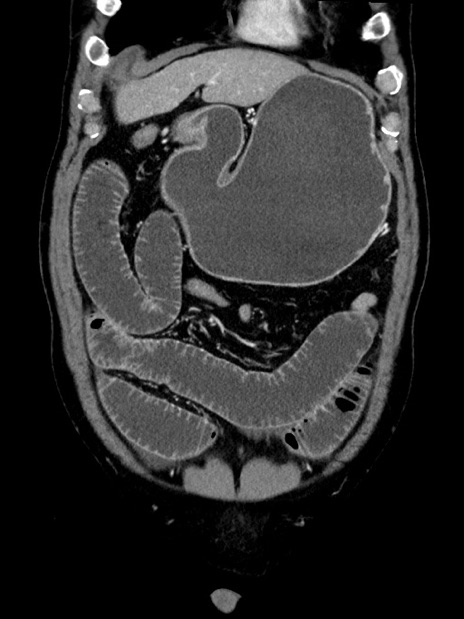

横断像

症例35(冠状断像)

【症例】70歳代 男性

【主訴】腹部膨満、嘔吐

【現病歴】昨日より腹部膨満感出現。本日増悪し、仙痛出現。嘔吐あり、受診。

【既往歴】糖尿病、胆摘後

【身体所見】BP 149/80mmHg、HR 74/min、BT 35.9℃、腹部:膨満、軟、圧痛なし。腸雑音減弱あり。上腹部正中切開瘢痕あり。

【データ】WBC 13500、CRP 1.72